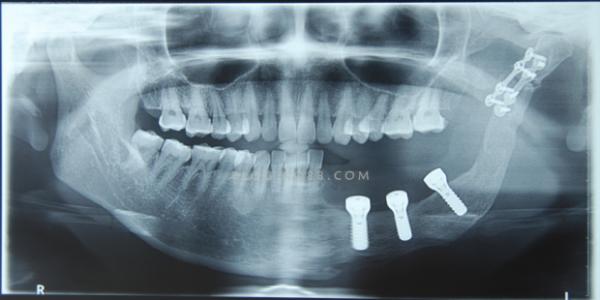

好多香港朋友都預約維港口腔植牙,大家都知植牙程式相對會復雜,從香港過嚟一次會花費較多時間,所以大家都想第一次過嚟能當日剝牙當日種牙最好,咁深圳維港口腔做一隻植牙要幾錢?

維港口腔植牙醫生表示,嚴重齲壞嘅牙齒若無法保留,可以進行剝牙後進行植牙修復。即剝即種技術現目前已經較成熟,不過需要注意唔係每個人都適合即剝即種嘅方式。大牙即刻種植嘅適應症主要包括以下幾點:

1、因齲病、牙隱裂、牙根縱裂等無法保留的後牙;

2、根尖周無急性炎症;

3、唇頰側及舌齶側骨壁完整,最好厚度大於2mm;

4、種植體可以接受良好三維位置的安排;

5、具備能夠提供良好初期穩定性的根尖骨或牙槽間隔。

具體是否適合做即剝即種需要醫生全面評估,維港口腔植牙配備多個植牙品牌,滿足不同人群嘅個性化需求。韓國種植牙5180元,韓國親水種植牙6580元,法國種植牙7990元,德國種植牙8800元,瑞士、瑞典種植牙9800元等,具體適合邊種種植牙品牌需要根據缺牙位置嘅牙骨牙周條件,高度寬度等多個因素來確定,如果有植牙嘅打算可以進一步咨詢維港口腔客服人員預約時間過來畀醫生詳細評估瞭解植牙方案。